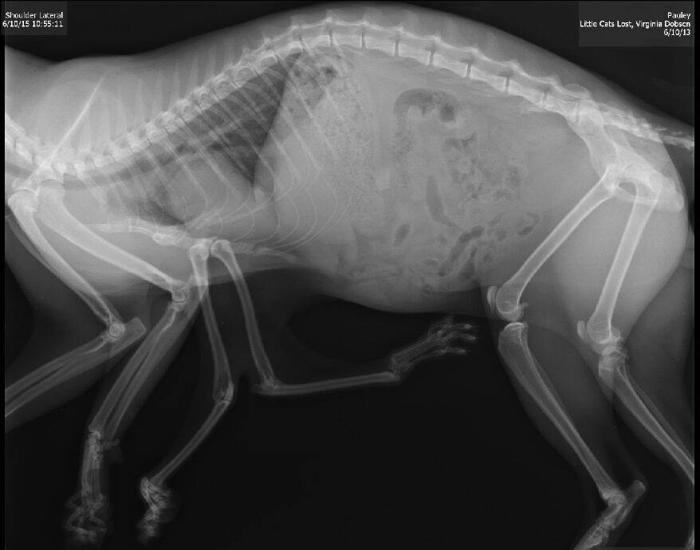

EDMONTON (CANADA) – Pauly è un gatto che ha sei zampe a causa di una patologia che colpisce un gatto su diecimila. La patologia consiste nell’assorbire parte del corpo di un altro gattino che si trovava con Pauly all’interno dell’utero della mamma. Pauly è stato trovato in strada nella parte sud ovest della città canadese di Edmonton alla fine di aprile ed è stato curato da alcuni abitanti fino alla fine di giugno. Il gatto aveva infatti mostrato fin da subito evidenti difficoltà nella deambulazione, il motivo per cui il micio è stato probabilmente abbandonato in strada.

“La particolarissima situazione di Pauly non rappresenta una novità solo per i volontari di Little Cats Lost, ma anche per il dottor Tamer. E’ infatti la prima volta che si prepara ad intervenire su un caso complesso e raro come quello di Pauly. “Questo caso è molto raro – spiega. E’ probabile che dentro l’utero della madre ci fossero due gattini, e che uno abbia assorbito l’altro. Ecco perché questo gatto ha sei zampe”. La particolarissima situazione di Pauly non rappresenta una novità solo per i volontari di Little Cats Lost, ma anche per il dottor Tamer. E’ infatti la prima volta che si prepara ad intervenire su un caso complesso e raro come quello di Pauly. “Questo caso è molto raro – spiega. E’ probabile che dentro l’utero della madre ci fossero due gattini, e che uno abbia assorbito l’altro. Ecco perché questo gatto ha sei zampe””.